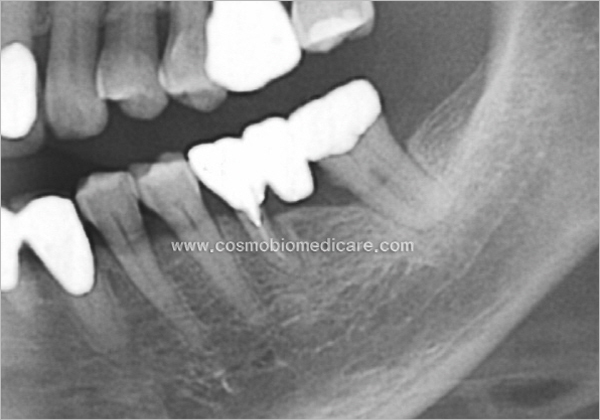

Clinical Cases

• Case3